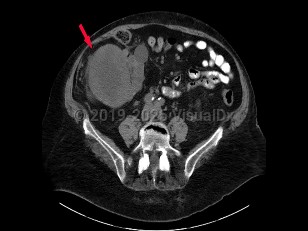

Renal cell carcinoma (RCC) accounts for the majority of malignant neoplasms arising from the kidney. RCC is often asymptomatic until significant disease advancement, with 1 in 4 patients having advanced local disease or distant metastasis at presentation. Peak incidence is between the ages of 50 and 70 years, with a male-to-female ratio of 2:1. Risk factors for development of RCC include cigarette smoking, acquired cystic disease of the kidney, hypertension, obesity, occupational exposure (asbestos, cadmium, lead, petrochemicals), and von Hippel-Lindau syndrome.

Clinical presentation includes hematuria, abdominal pain, flank mass or abdominal mass, fever, weight loss, anemia, or varicocele. Many patients have tumors discovered incidentally with abdominal imaging performed for another reason.